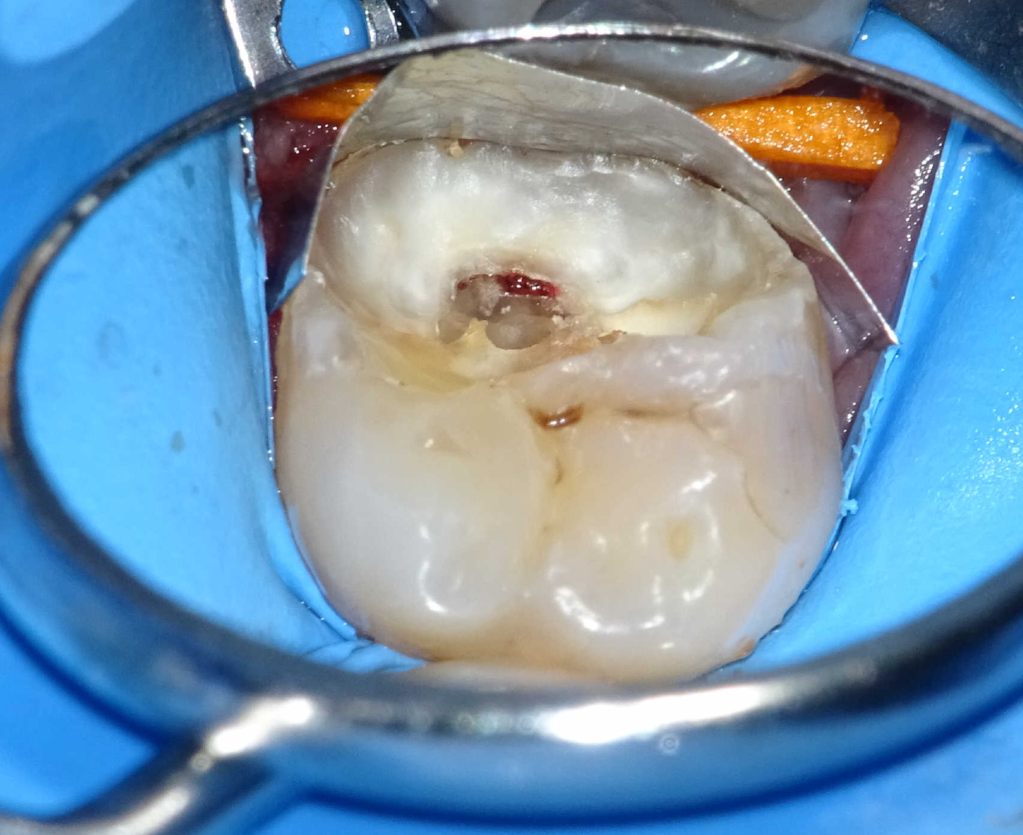

Pulpotomía biodentine + reco preendio